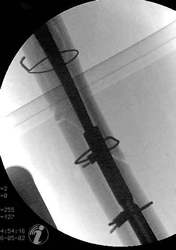

Ein Femurnagel wurde so zugerichtet, dass mit ihm die Prothesenspitze in einer Länge von 8 cm aufgefädelt wurde. Der Nagel wurde durch das Knie hindurch eingebracht. Distal wurde der Nagel verriegelt. Belastungsstabilität lag vor.